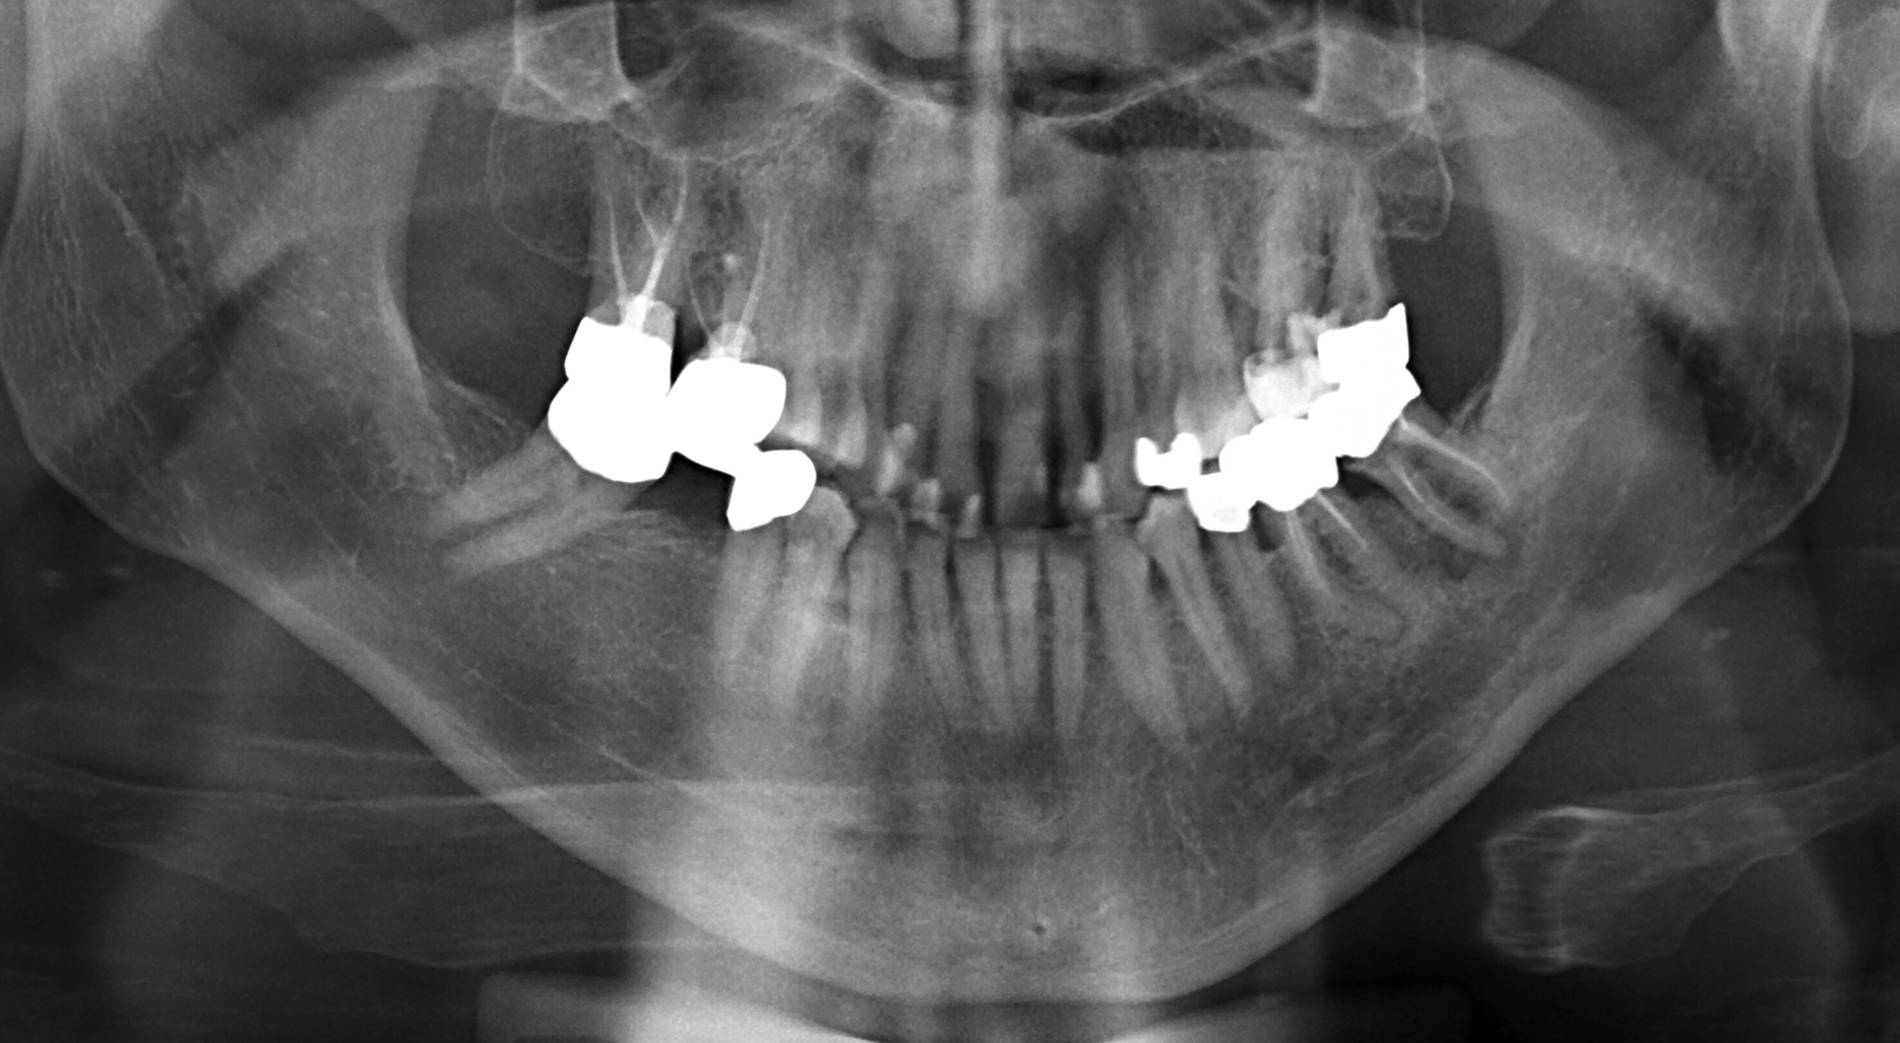

Es präsentierte sich ein Patient in gutem Allgemein- und Ernährungszustand. Relevante Vorerkrankungen ließen sich nicht eruieren. Klinisch zeigte sich eine derb palpable Schwellung der linken Wange mit Adhärenz nach enoral (Abbildung 1). Sonografisch ließ sich ein echoarmes Grundmuster mit Binnenreflexen und unregelmäßiger Wandstruktur darstellen (Abbildung 2). In der anschließenden radiologischen Diagnostik zeigte sich ein periapikal osteolytisch veränderter Knochen im Bereich des Zahnes 37 (Abbildung 3). Nebenbefundlich präsentierte sich eine beginnende apikale Aufhellung an der mesialen Wurzel des Zahnes 36 mit Verdacht auf inkomplette Wurzelkanalfüllung. Die erweiterte Diagnostik mittels Digitaler Volumentomografie offenbarte eine Osteolyse der vestibulären Lamelle in Regio 37 (Abbildung 4). In Zusammenschau der Befunde wurde die Verdachtsdiagnose einer chronisch entzündlichen Veränderung nach Partsch gestellt.